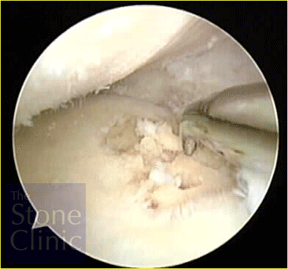

This next photo on the right shows the meniscal allograft in place. The meniscal allograft is the structure to the right of the photo. Above it is the rounded end of the femur and below is the flattened top of the tibia - the tibial plateau.